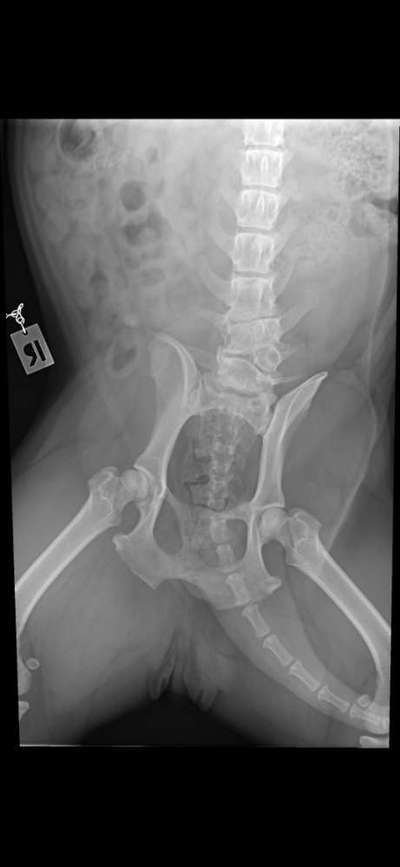

Anbei die Bilder, die zeigen wo die Bandscheibenvorfälle und der malformierten Wirbel liegen.

Ich werfe mich nochmal schnell dazwischen, um die Fragen noch zu beantworten. Es gab keine OP, es stand kurz mal zur Debatte, aber selbst die Klinik konnte nicht sagen, welche der vielen Baustellen ihr die Schmerzen bereiten, und alles zu beheben wäre ein Ding der Unmöglichkeit. Die Bilder sind bereits 2 Jahre alt und zumindest gab es keine Verschlechterung. Wir versuchen es also weiterhin mit Physio und Schmerzmitteln in den Griff zu bekommen. Anbei die Bilder, die zeigen wo die Bandscheibenvorfälle und der malformierten Wirbel liegen. Aber es darf jetzt gerne erstmal um die anderen Hunde hier gehen.

HWS + LWS ✔️

+ BWS 🙉